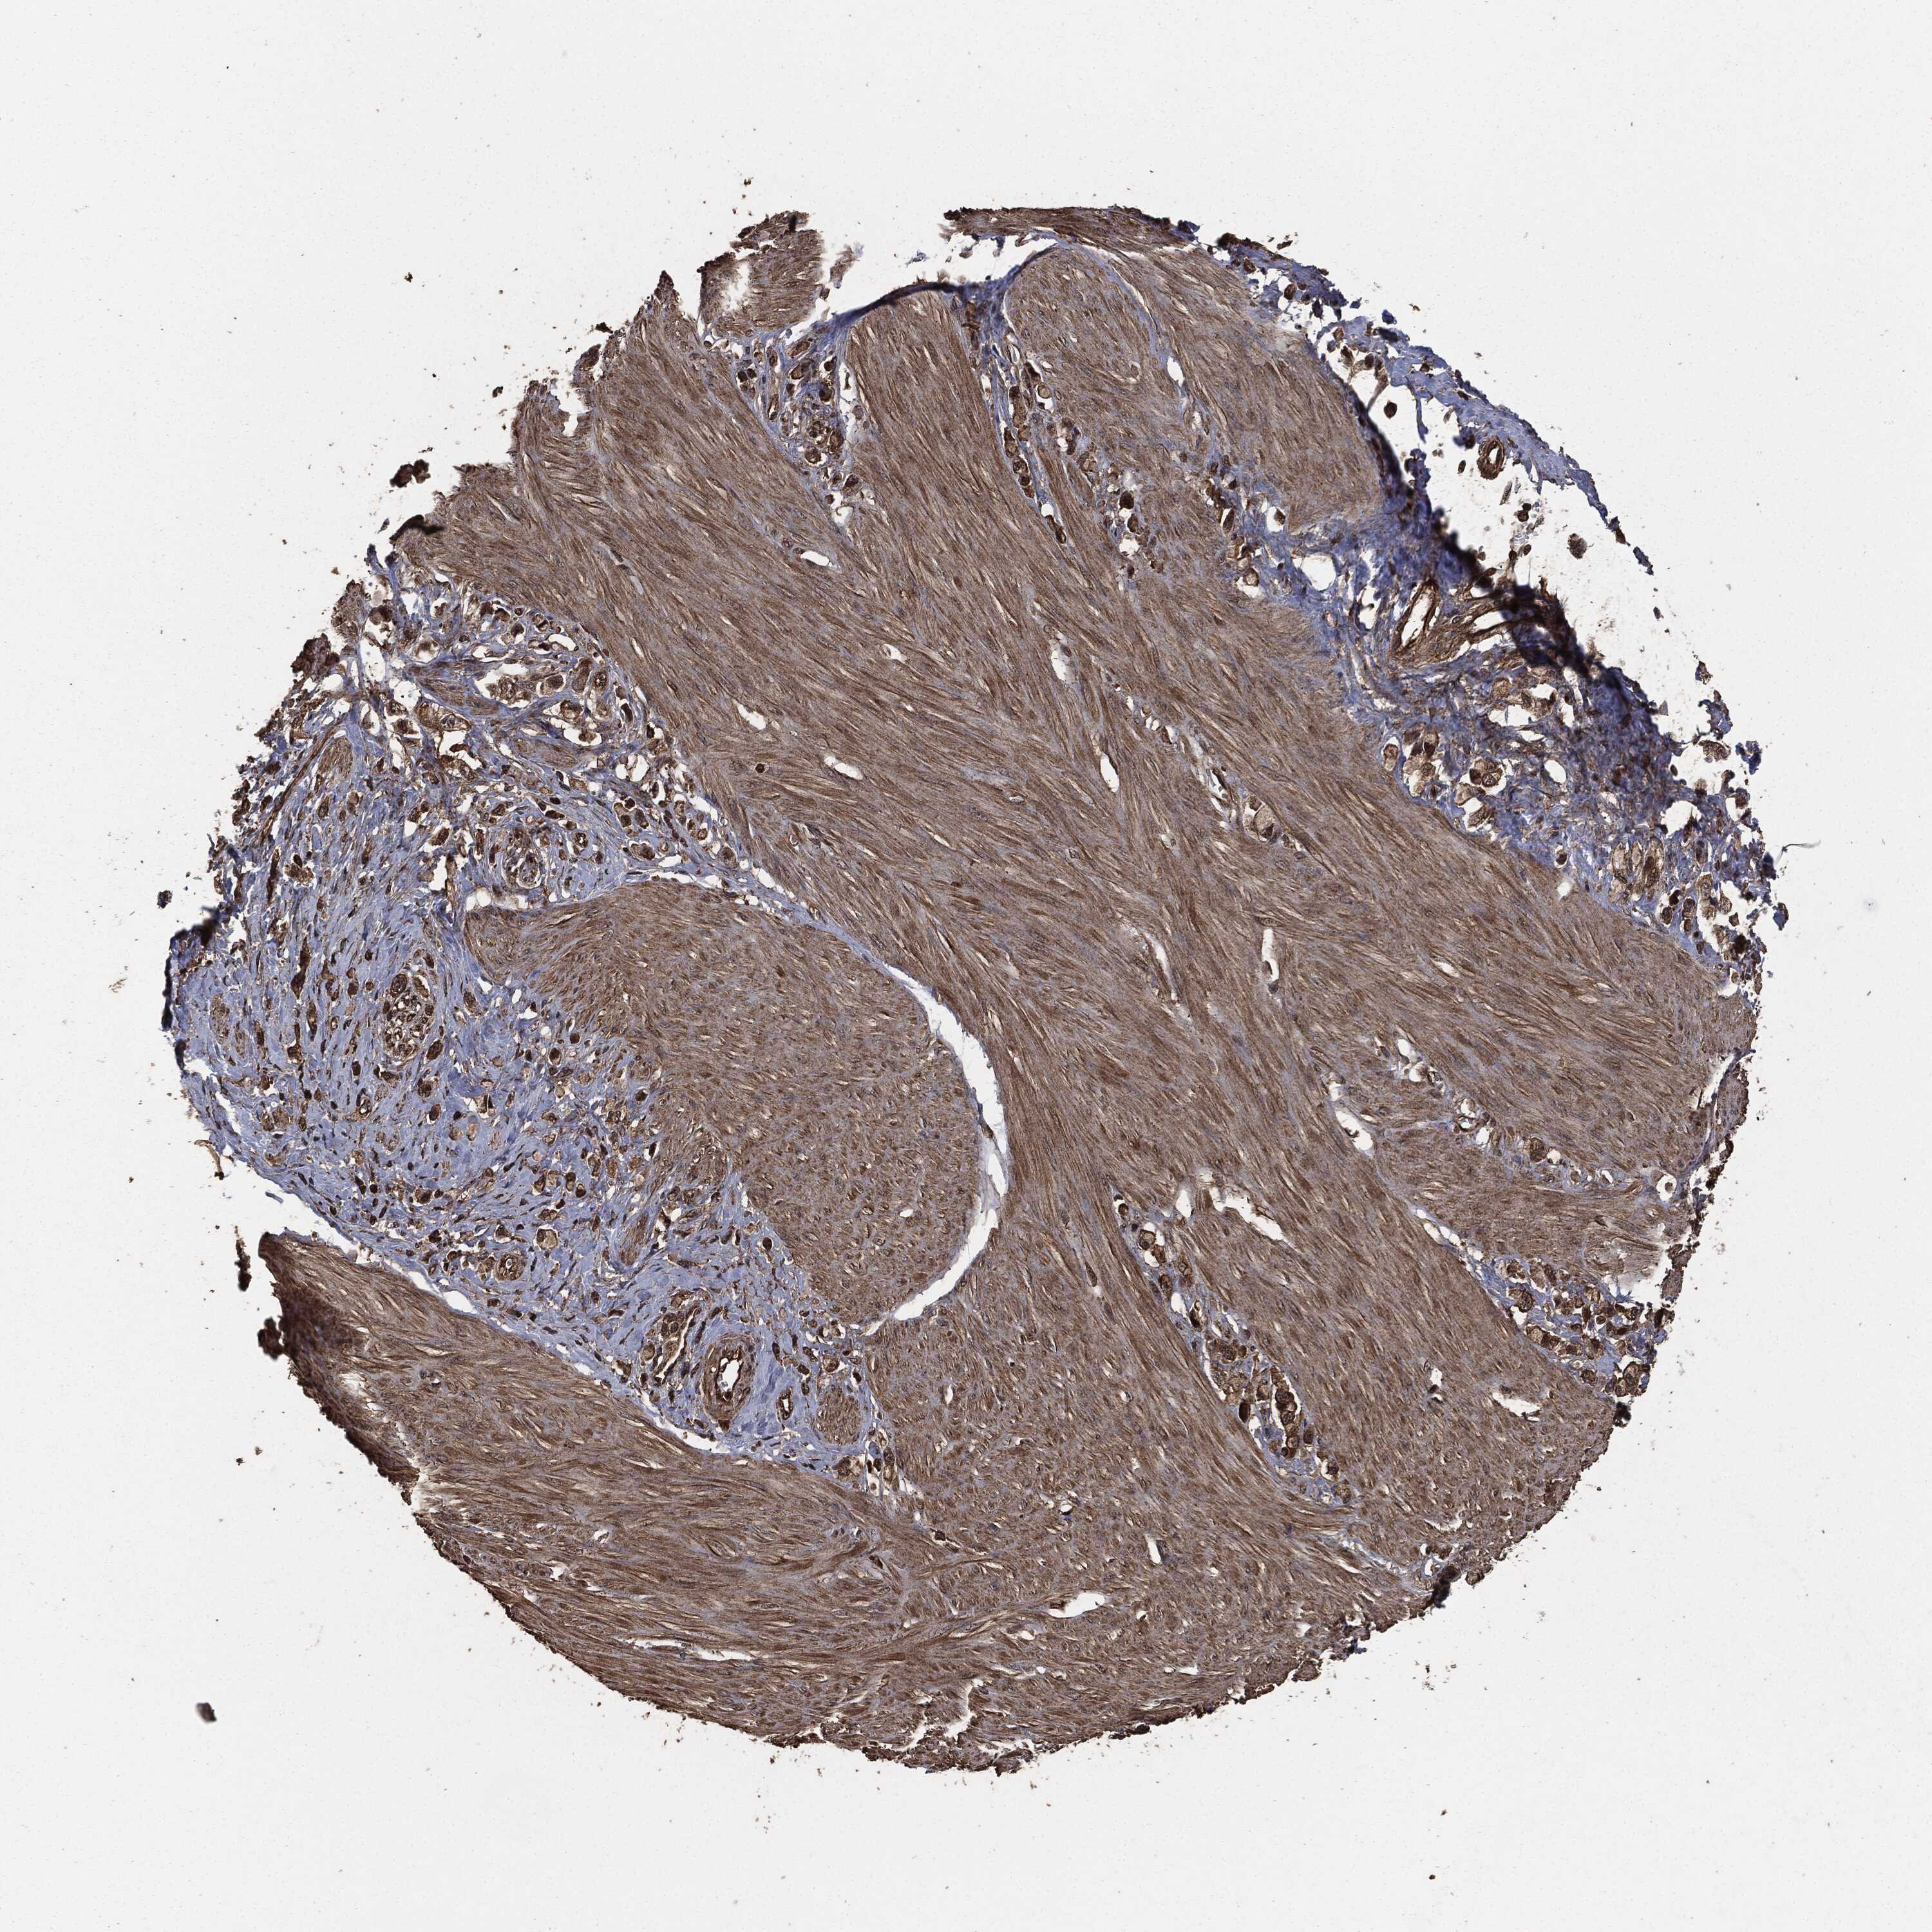

STOMACH CANCER - Protein expressioni

A mouse-over function shows sample information and annotation data. Click on an image to view it in a full screen mode. Samples can be filtered based on level of antibody staining by selecting one or several of the following categories: high, medium, low and not detected. The assay and annotation is described here.

Note that samples used for immunohistochemistry by the Human Protein Atlas do not correspond to samples in the TCGA dataset.

Antibody stainingi

Antibody staining in the annotated cell types in the current human tissue is reported as not detected, low, medium, or high, based on conventional immunohistochemistry profiling in selected tissues. This score is based on the combination of the staining intensity and fraction of stained cells.

Each image is clickable and will lead to virtual microscopy that enables deeper exploration of all samples and also displays staining intensity scores, fraction scores and subcellular localization as well as patient and tissue information for each sample.

Staining

High

Medium

Low

Not detected

Intensity

Strong

Moderate

Weak

Negative

Quantity

>75%

75%-25%

<25%

None

Location

Nuclear

Cytoplasmic/membranous

Cytoplasmic/membranous,nuclear

Adenocarcinoma, NOS

Adenocarcinoma, High grade